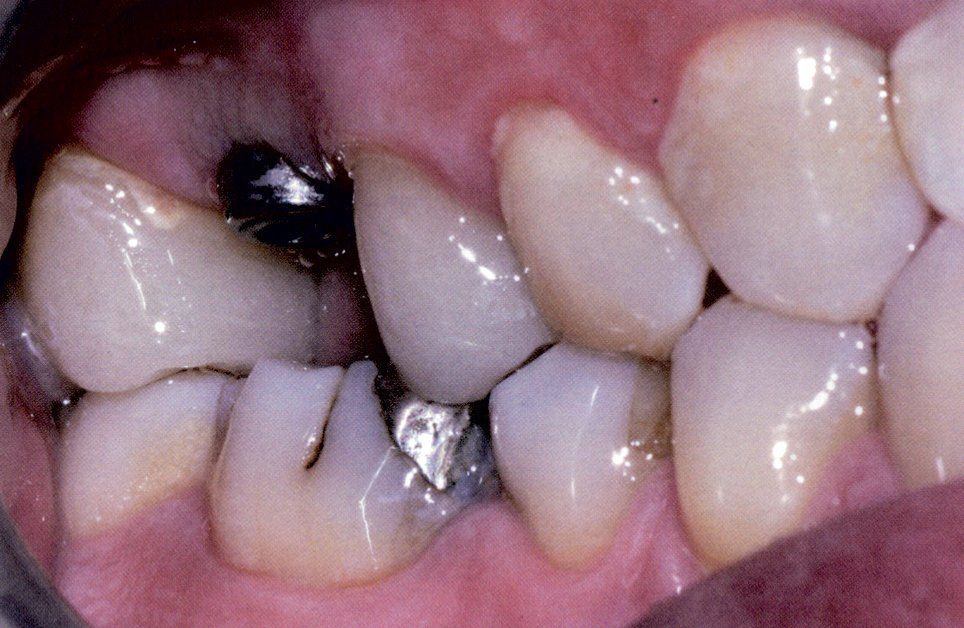

Sostituzioni immediate di denti

Sostituire denti mancanti è possibile grazie alle tecniche acquisite nel campo dell'implantologia, la branca del settore odontoiatrico che si occupa di inserire protesi fisse o impianti dentari.

In un'unica seduta si può entrare in studio senza denti ed uscire con un bel sorriso.

Il risultato finale è straordinariamente naturale e apporta non solo benefici estetici ma, soprattutto, cambia radicalmente lo stile di vita, apportando vantaggi sul benessere totale della persona.